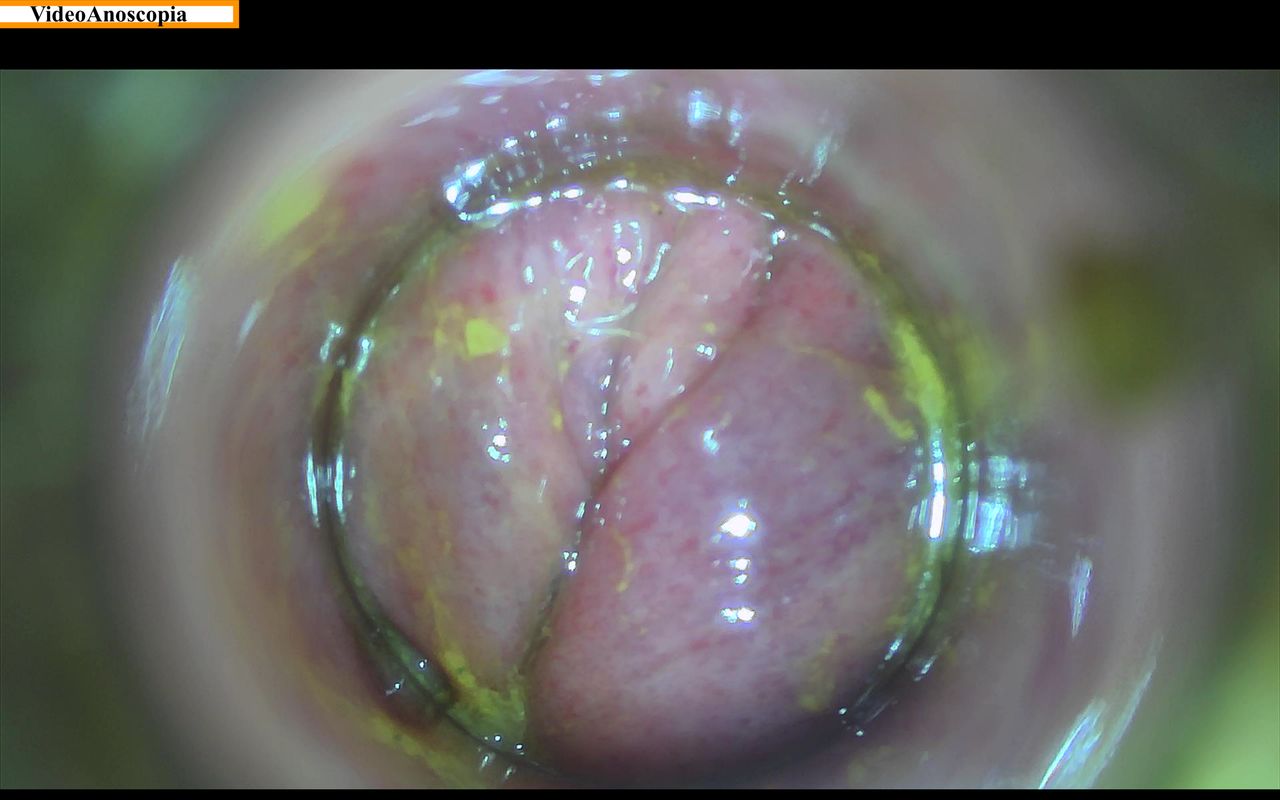

• Esami: Videoanoscopia, Ecografia addome completo, ecografia inguinale e delle anse intestinali.